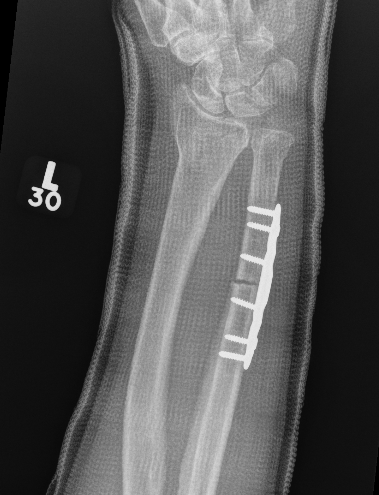

Xray

Bilateral xrays

PA film in neutral

- wrist neutral

- elbow & shoulder at 90°

CT

Ulnar Shortening

Indications

Short radius, positive ulna variance

Acceptable alignment distal radius

Acceptable DRUJ

Technique

Approach to ulna

- between ECU and FCU

- can use cutting jigs

- resect 2 - 6 mm of ulna based on xray templating

- compression plate